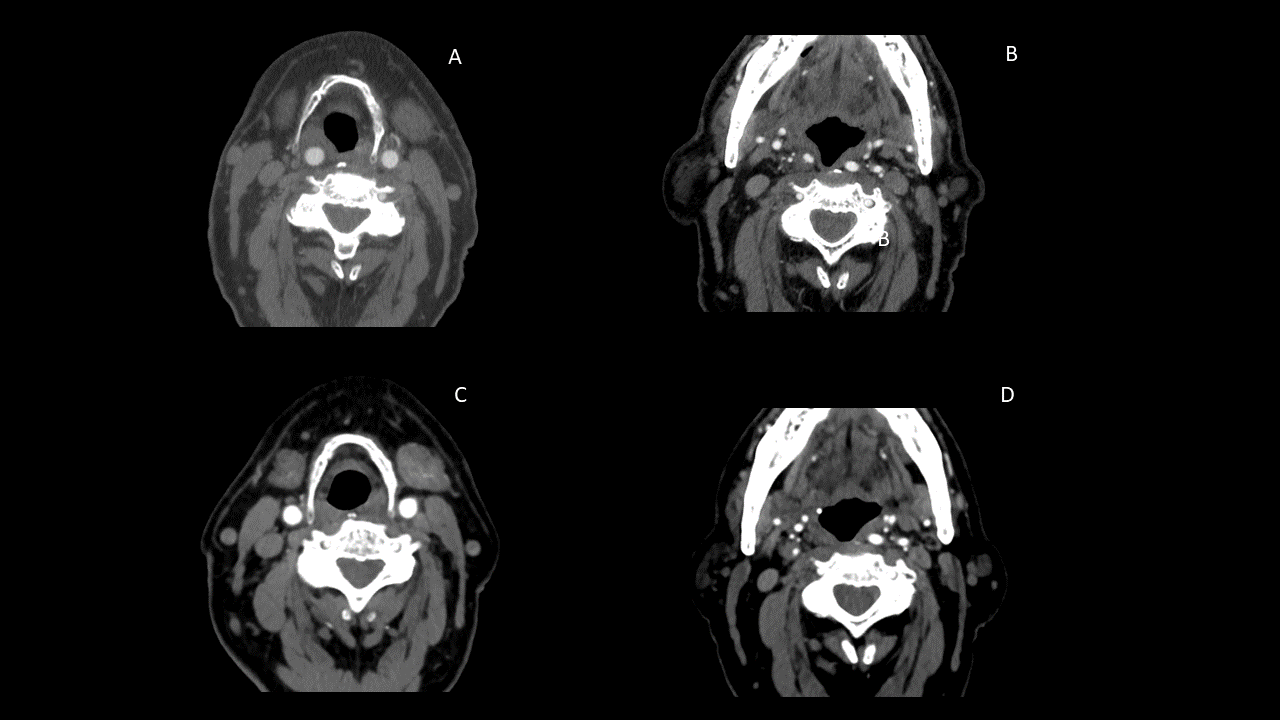

ig. A-B. AngioTC inicial muestra trayecto retrofaríngeo de arteria carótida común (a la altura de hiodes) e interna derecha (improntando pared posterior faríngea derecha).

Fig. C-D. AngioTC de control que muestra lateralización de arteria carótida común e interna derecha (con desaparición del trayecto retrofaríngeo). Además existe progresión del grado de estenosis.